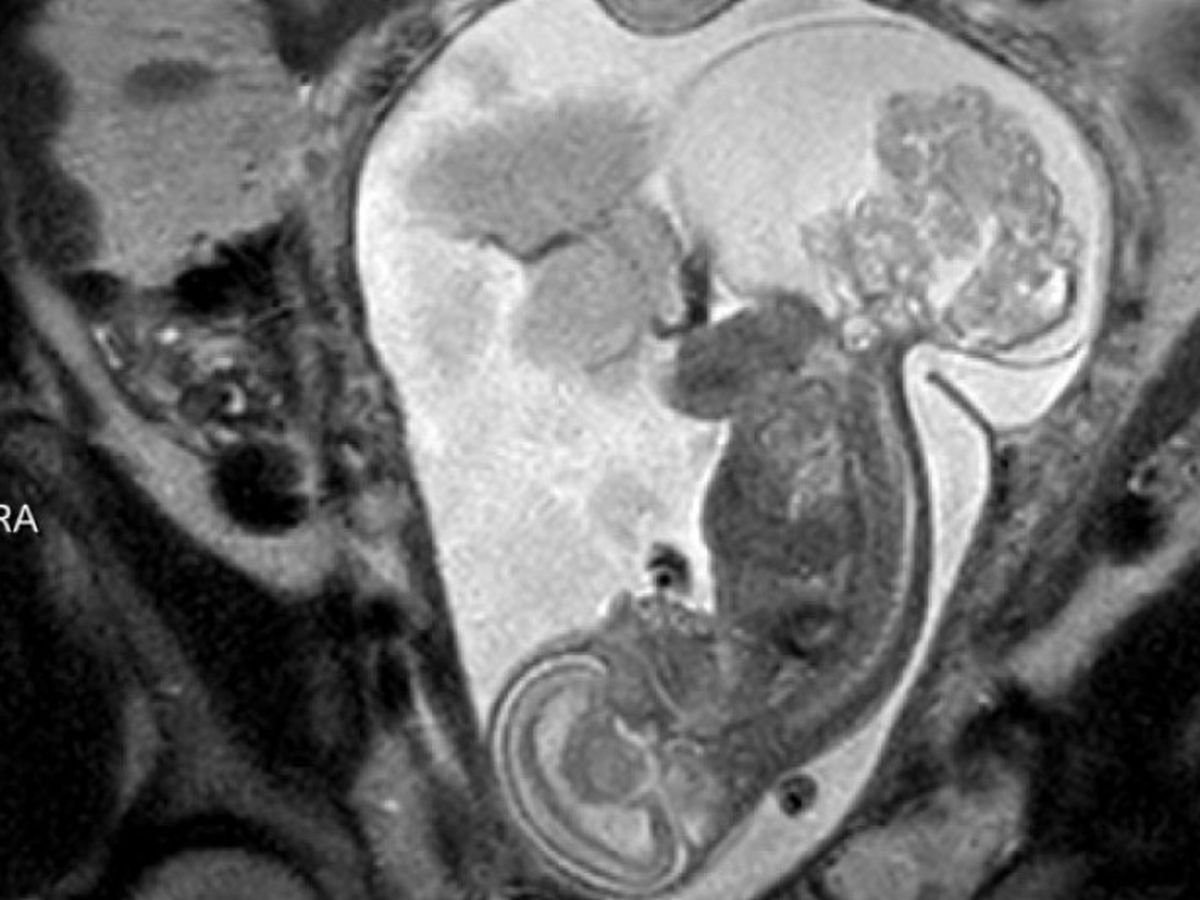

At 20 weeks we came to Houston for several tests including MRI, Ultrasounds, Echocardiograms, and meetings with the specailists at both Houston hospitals. At one hospital we were strongly encouraged to terminate the pregnancy due to the extremely large size of our baby's tumor and the risks to my health. Texas Children's gave us a more positive yet realistic option of having Open Fetal Surgery to remove a large portion of Lynlee's tumor to try to save her. They told us she had a 50% chance of making it with the surgery. Jeff and I were in agreement that termination was not an option and we wanted to give Lynlee a chance at life by going with Texas Children's and having Open Fetal Surgery.

On March 7th at 23 weeks 5 days I was taken into emergency Open Fetal Surgery because Lynlee's turmor was taking the majority of her blood supply and causing her to go into cardiac failure. The doctors cut me open a little larger than a C-Section and removed my uterus. They then made a very large incision in my uterus to access Lynlee and to attempt to remove the tumor. The tumor was so large they had to puncture the fluid filled part and then cut out the vascular part of the tumor. The doctors were successful in removing 90% of the tumor. It was a shock to Lynlee's system so they did have to help restart her heart and give her a blood transfusion. Once she was stable they put her back in and sewed up my uterus and abdomen. Then it became a wait and see game. The next few days were very critical and I remained in the hosptial for a week. Lynlee slowly recoved from the invasive surgery and began having a normal heartbeat.